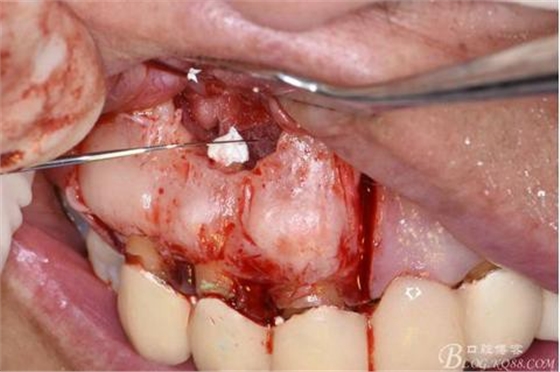

圖15.取愛如特生物陶瓷材料

圖16.放置在干燥好的根管內(nèi)

圖17.根尖倒充填完畢

圖18.骨腔填塞膠原蛋白海綿